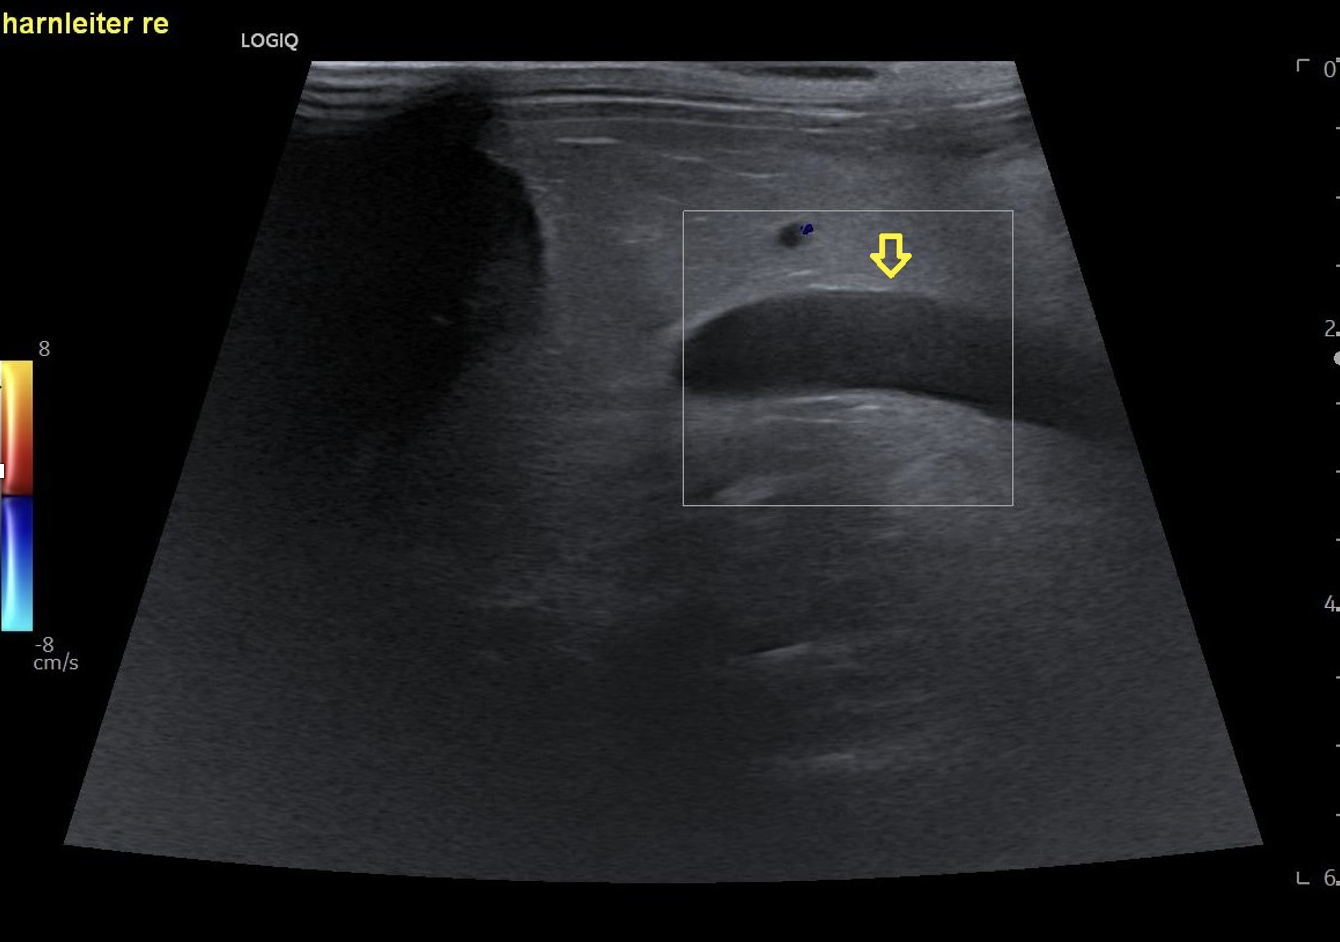

Die Röntgenuntersuchung zeigte eine weichteildichte Masse im rechten mittleren Abdomen sowie eine radiodichte Struktur dorsal der Harnblase. Die Sonographie ergab eine deutlich veränderte rechte Niere mit hochgradiger Hydronephrose sowie eine ausgeprägte Peritonealreaktion. Der rechte Ureter war stark dilatiert mit einer schallschattenbildenden Struktur kurz vor der Einmündung in die Harnblase. Die linke Niere sowie der linke Ureter waren sonographisch unauffällig. Auf Basis dieser Befunde wurde die Diagnose einer hochgradigen rechtsseitigen Hydronephrose sekundär zu einer Ureterolithiasis gestellt.